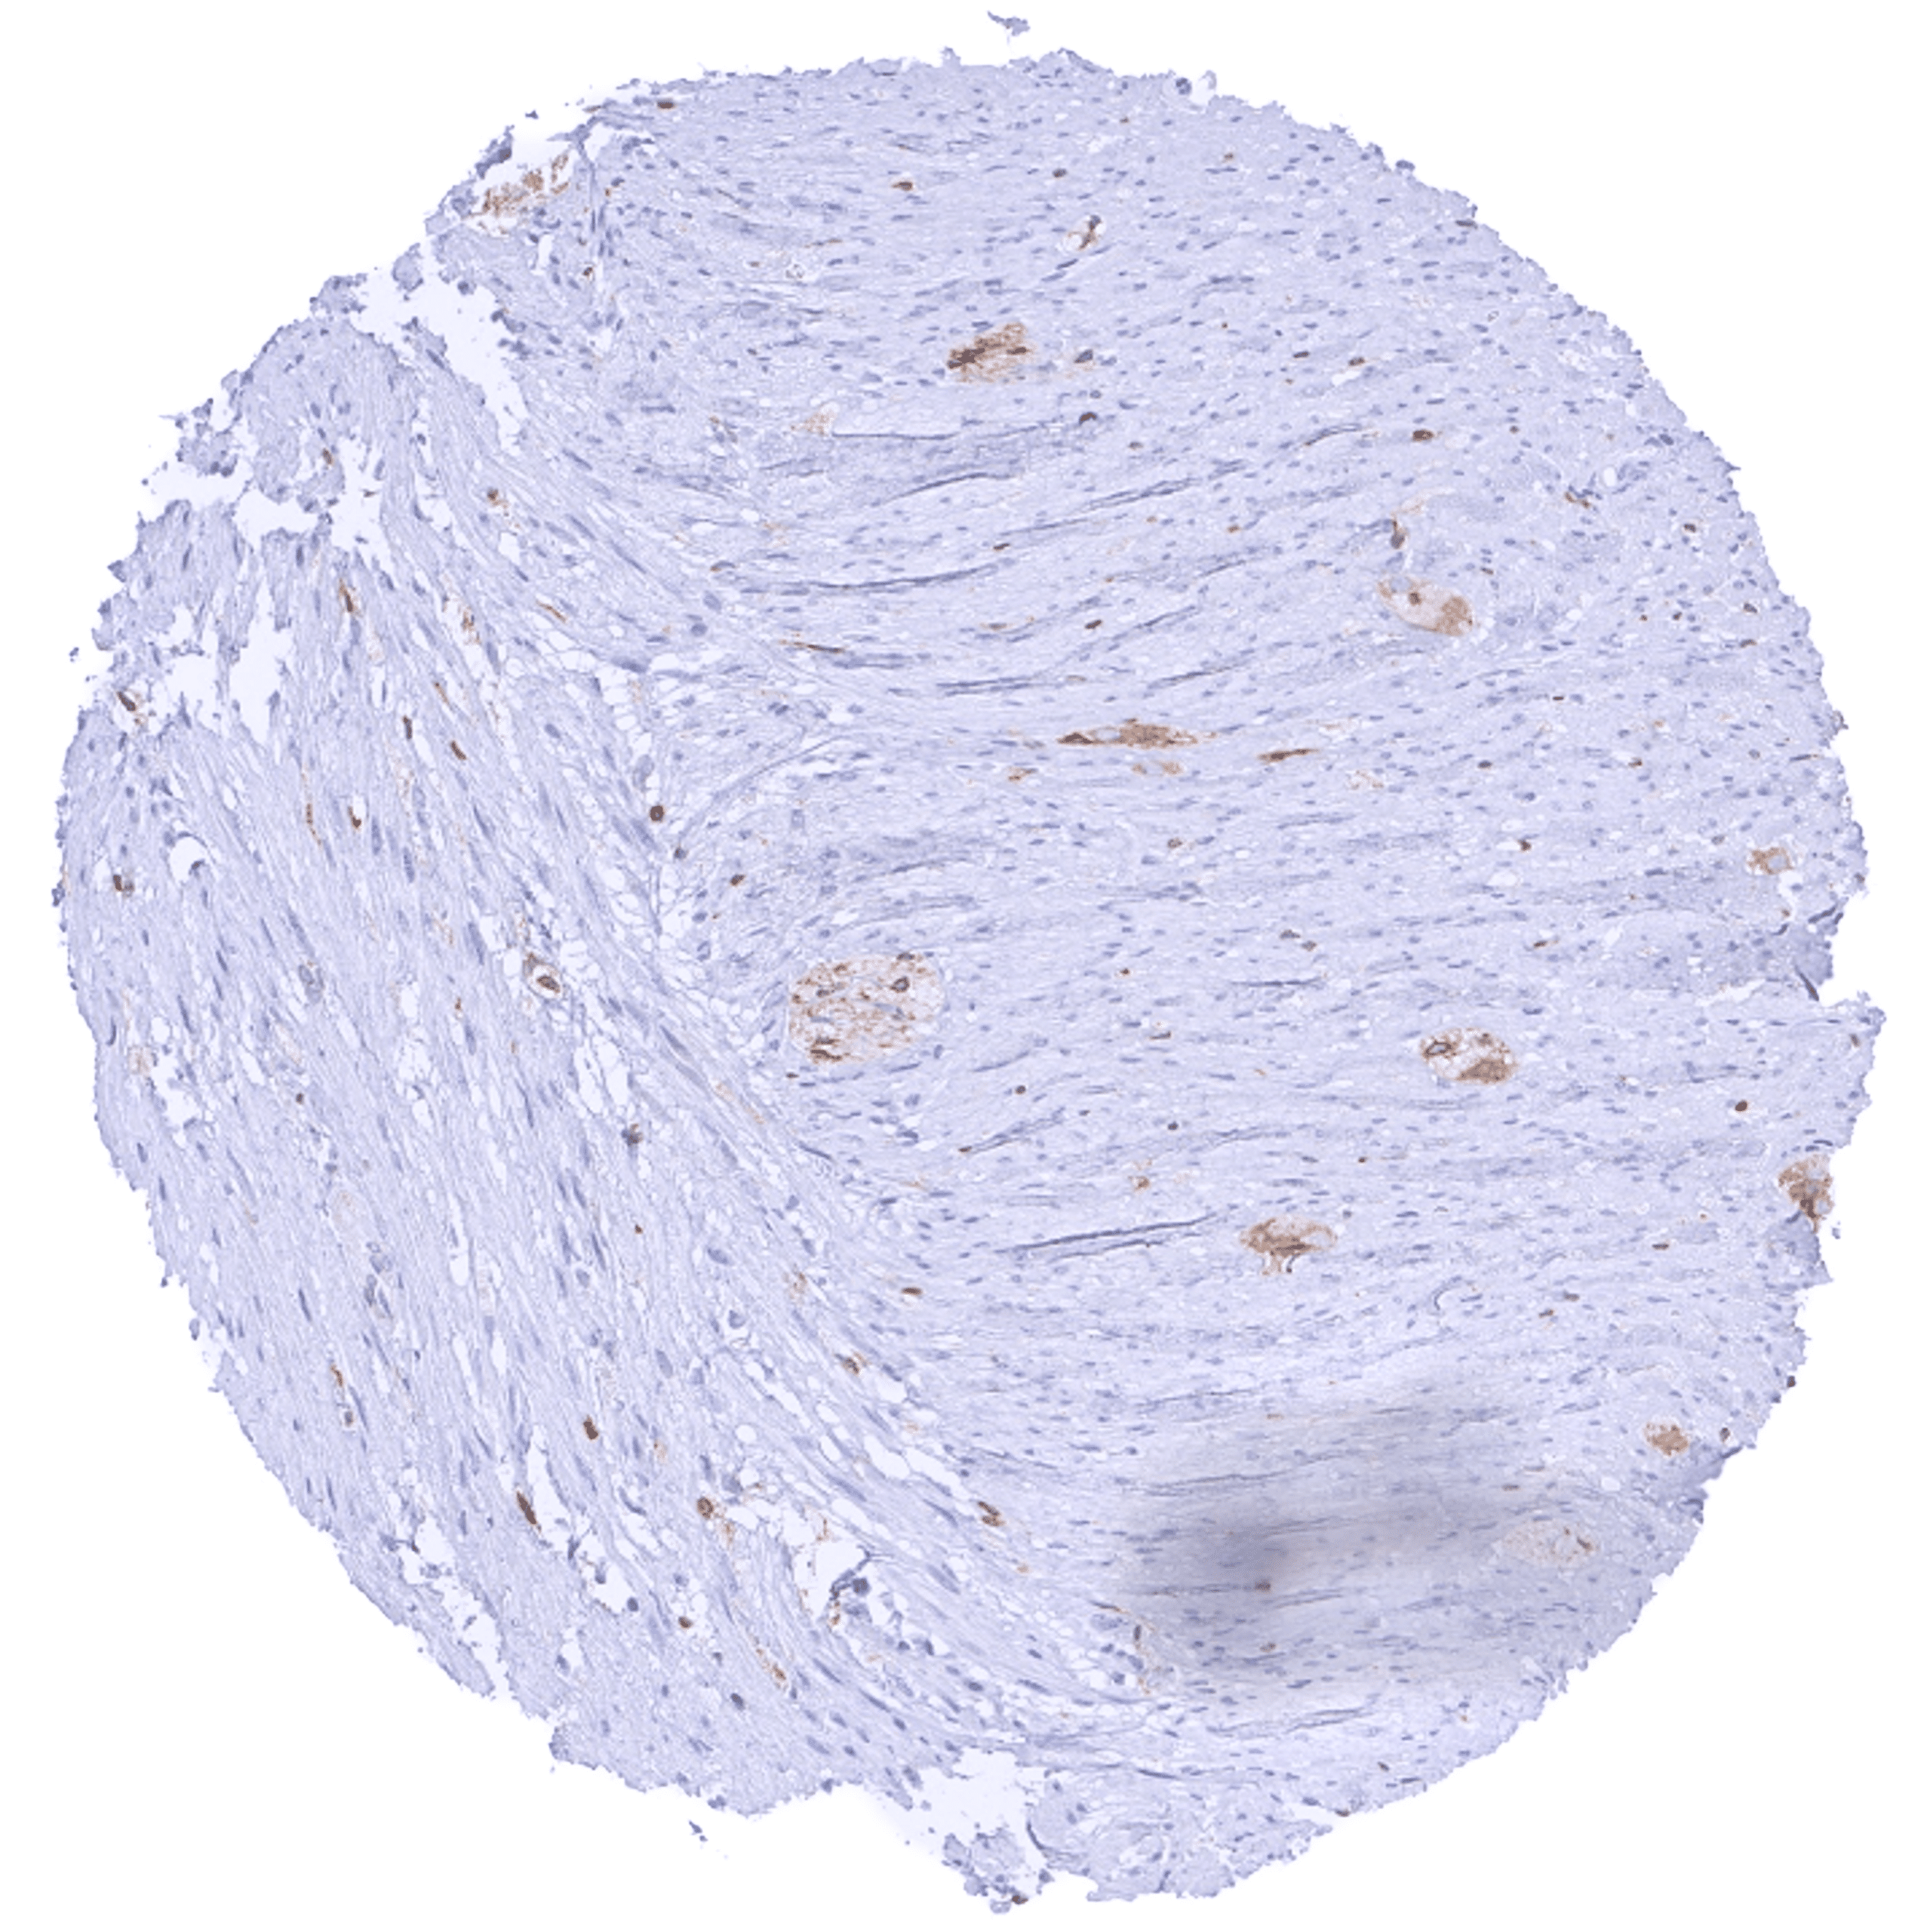

| Muscle/connective tissue | Heart muscle | Negative. |

| Smooth muscle | A faint cytoplasmic bcl-2 staining of muscle fibers can occur in some cases. | |

| Stroma | Negative or faint bcl-2 staining. | |